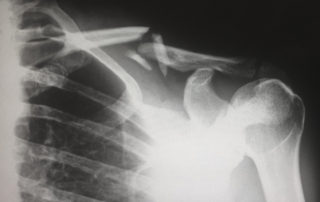

Injuries from a car accident

The Pottenger Law Firm is very experienced in representing those injured in car accidents. Throughout the Kansas City area, thousands [...]